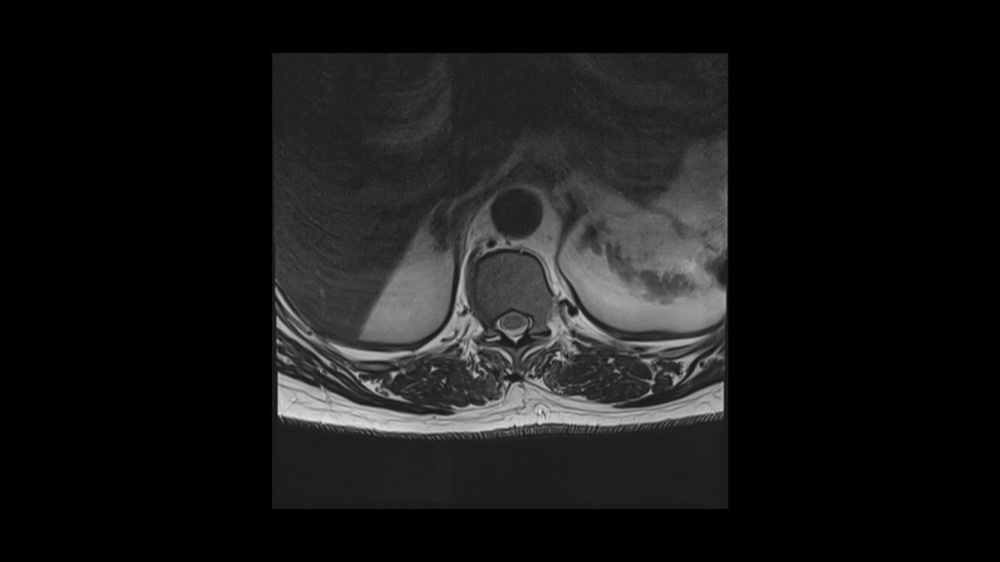

Marcilhacy / Dion / Kirchner / Oufighou / Tordjman 11/01/2023